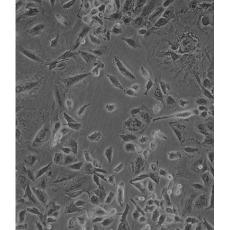

NCI-H1975

中文名稱 人肺腺癌細胞

組織來源 肺腺癌;女性

生長特性 adherent

形態(tài)特征 epithelial

細胞描述 該細胞是1988年7月從一名女性(無抽煙史)非小細胞肺腺癌組織中分離得到的。